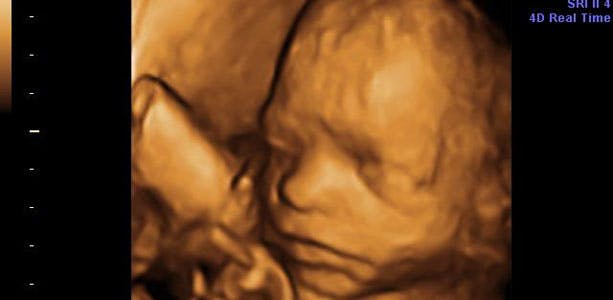

Gravid uge 27: Smager på fostervandet

Smagsløgene er ved at være færdigudviklede, og barnet reagerer på smagen af fostervandet med flere eller færre synkebevægelser afhængigt af, hvilken smag fostervandet har. Søvnperioderne er nu mere sammenhængende og måske endda som dine egne. I slutningen af ugen måler barnet cirka 33 centimeter og vejer omkring et kilo. Lårbenet måler cirka fem centimeter og hovedet cirka syv centimeter.